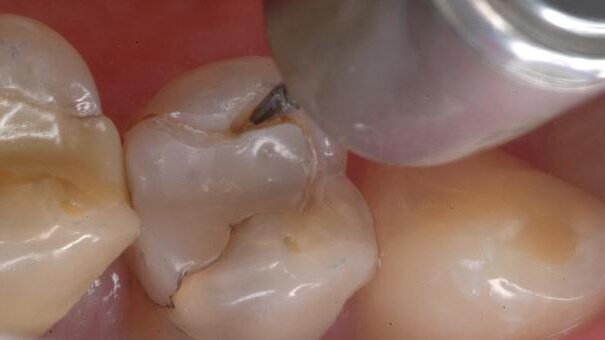

1. The occlusal margins of a composite restoration have begun to break down. There is no radiographic evidence that decay has spread far beyond the surface (Fig. 3).

2. All decay and questionable tooth material are removed with the Fissurotomy Bur (Fig. 4).

3. The perimeter preparation is examined for any remaining decay (Fig. 5).